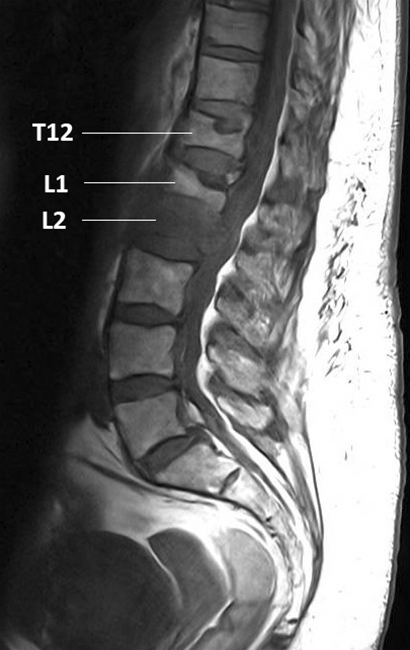

L’IRM rachidienne réalisée montre l’image suivante et le radiologue confirme le caractère suspect de malignité de la fracture. L’examen clinique de la patiente est inchangé. La masse pulmonaire a été biopsiée et vous êtes en attente des résultats. Figure 3 (Salomé Abdellaoui, La Revue du Praticien)

Figure 4 (Salomé Abdellaoui, La Revue du Praticien) L’imagerie montre une fracture de L2 en hyposignal T1 avec un recul du mur postérieur, ainsi que des fractures consolidées des plateaux vertébraux supérieurs de T12 et L1. Les fractures suspectes avec recul du mur postérieur sont réputées instables et nécessitent un avis orthopédique avant d’autoriser la mobilisation. En attendant l’avis ou en cas de fracture instable, on recommande un repos au lit strict et des mobilisations avec port d’un corset rigide. Un avis oncologique est recommandé devant cette forte suspicion de néoplasie, afin d’orienter la prise en charge et de débuter le suivi par une équipe dédiée. La biopsie est indispensable pour confirmer le diagnostic de cancer, mais le traitement ne pourra (dans l’immense majorité des cas) être débuté qu’après réception des résultats histologiques.